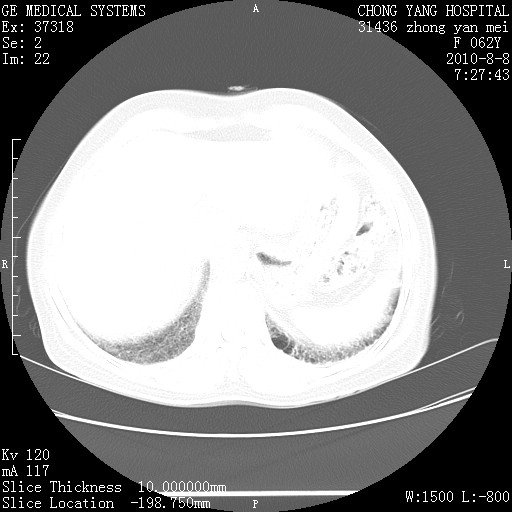

标题: CT28269:F62Y咳嗽胸痛数月。 [打印本页]

标题: CT28269:F62Y咳嗽胸痛数月。

两肺弥漫性间质纤维化伴继发性支扩。

考虑特发性肺间质纤维化

考虑两肺间质性肺炎并肺间质纤维化。

双肺间质纤维化合并感染、肺气肿

另见右乳腺似有小钙化灶,建议进一步检查。

两肺间质纤维化并牵拉性细支气管扩张。

考虑两肺间质性肺炎并肺间质纤维化,肺气囊形成。